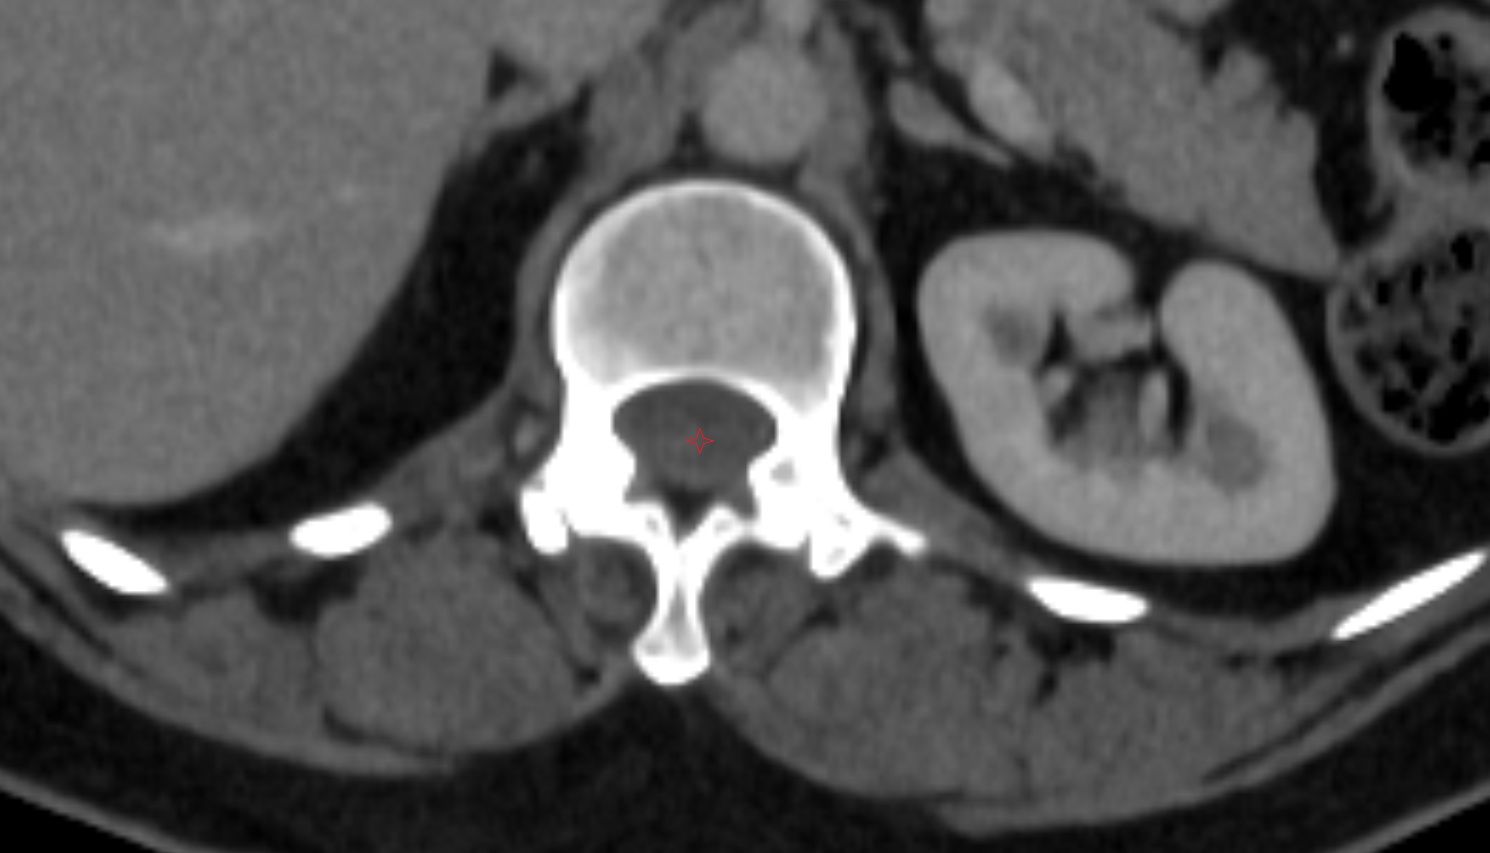

- Body of vertebra

- Right kidney

- Left kidney